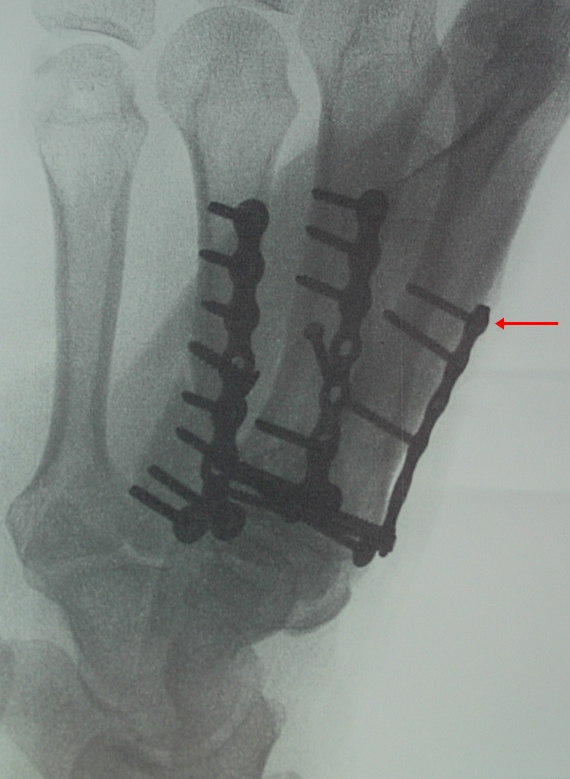

Remember this picture? Well, it gives you an idea of the hardware in my left hand. It's a result of this little accident in December 2011.

That screw there, marked with the red arrow--well, that is "supposed" to be a locking screw. It has started to

"back out" for some reason and is now protruding up on the back of my hand. Because it doesn't feel so good--just an odd deep ache, especially when I accidentally bump it on something and the plate is starting to move it must come out. Here's a different view before the screw started to move. Count them. Twenty screws. But only that one little stinker is loose--as far as the doctor can tell.